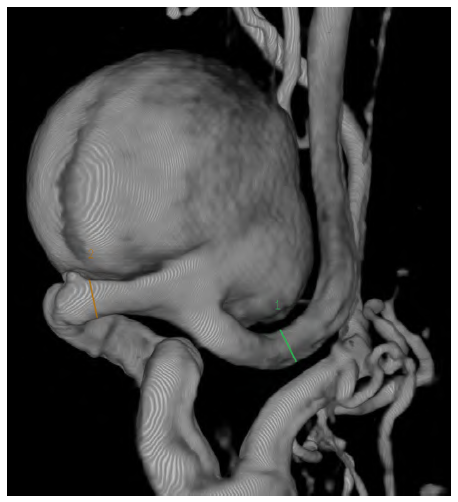

Computed tomography angiography (CTA) showed a saccular aneurysm of the left internal carotid artery with a significant tortuosity (Figures 1 and 2).

Figure 1 Preoperative computed tomography angiography reconstruction of the saccular internal carotid aneurysm

The aneurysm measured 28mm x 30mm and was located near the base of the skull, arising 30mm after the carotid bifurcation. The CTA had also highlighted significant tortuosity of the contralateral ICA but without aneurysmal degeneration. Because of the tortuosity of the ICA, not technically feasible for endovascular repair due to the diameter and absence of optimal distal neck, the volume of the aneurysm, and mass-related symptoms, open repair was preferred to endovascular exclusion as the latter (by excluding the ECAA with a covered stent or embolizing the aneurysm with coil spirals); would not address the mass effect and potential development of permanent cranial nerve injury.